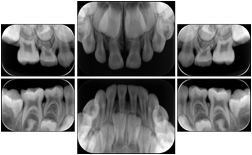

2. A patient requests cosmetic surgery to enhance their facial appearance. The case requires consultation between an orthodontist in New York and an oral surgeon in California. The cephalometric series of 2D projections constructed from a volumetric CT data set that is used for the discussion is arranged by a Structured Display for transfer between the two practitioners.

Cephalometric Series Structured Display

Figure OO-2. Cephalometric Series Structured Display